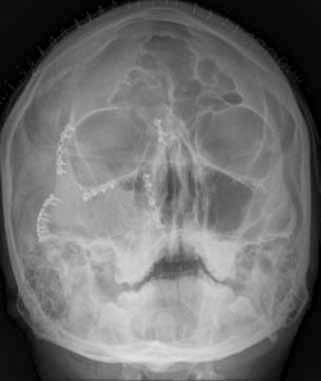

Complex facial fractures

Complex facial fractures 142 photos